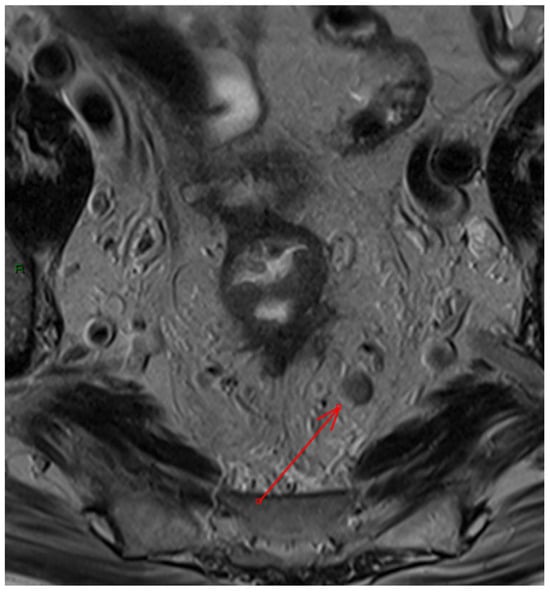

- Extramural vascular invasion as a harbinger of recurrence: The relationship between extramural vascular invasion (EMVI) and local recurrence brings to light the aggressive nature of such tumors. The presence of malignant cells in blood vessels beyond the muscularis propria near a colorectal tumor, indeed, is linked to more advanced tumors and it has been associated with a four-fold increased risk of distant metastases and a significant decrease in disease-free survival, dropping from 74% to 35% [37]. Thus, accurate histological reporting of EMVI is crucial and should be part of structured reporting.However, despite this strong association, there is still no consensus on how to tailor treatment strategies based on the positivity of this finding on MRI, and recommendations within the guidelines remain inconsistent [38,39]. EMVI is graded from 0 to 4, with grades 0–2 indicating better outcomes due to the absence of definitive vascular invasion, while grades 3–4 show vascular invasion and are linked to poorer outcomes. Furthermore, EMVI is also associated with higher TNM stage and mesorectal fascia involvement, though few studies have considered other MRI factors like tumor deposits or enlarged lateral lymph nodes, and, to the best of our knowledge, no study has investigated the variations in oncological outcomes between EMVI grades 3 and 4 [40]. The regression of EMVI following neoadjuvant treatment appears to have a positive impact on prognosis [41,42]. However, many studies evaluating EMVI regression are constrained by small sample sizes, which limits their statistical significance. Despite the prognostic significance of EMVI and the need to include it in structured reporting, further research is required to better inform treatment strategies.